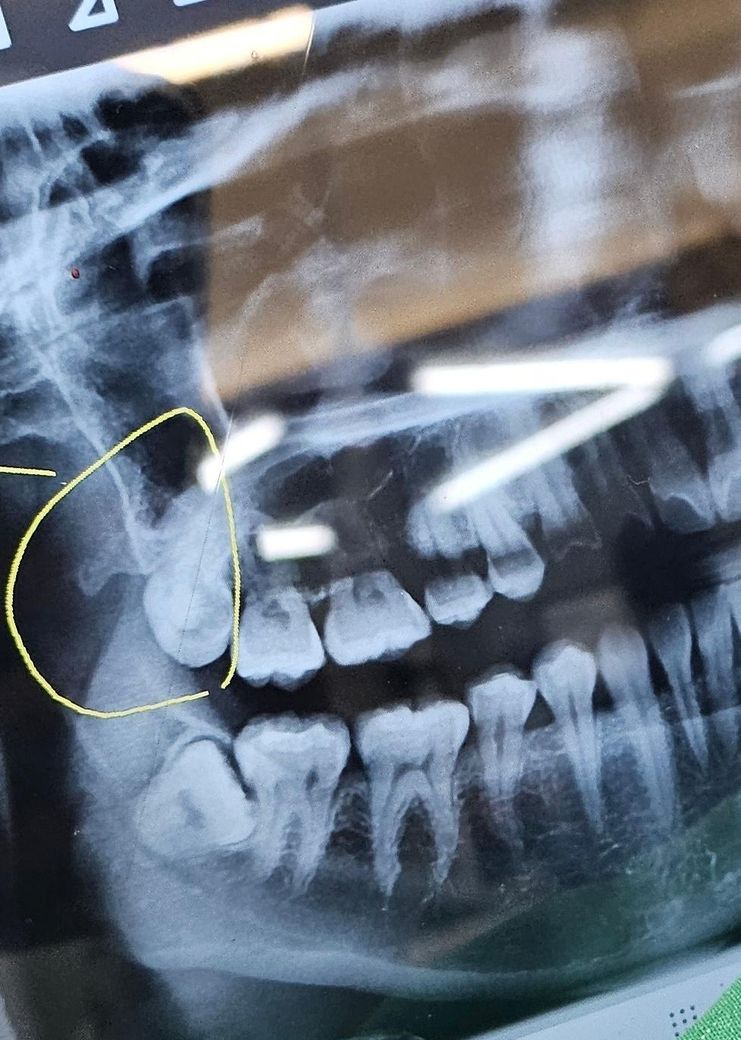

치과에서 위에 난 사랑니를 발치했습니다.

의사쌤께서 약간 입을 다물라고 하시고, 잇몸을 절개하지 않은 상태에서 윽 윽 두 번 정도 힘줘서 당기니(?) 사랑니가 뽑혔습니다.

5초 정도 걸린것 같은데 뿌리도 굉장히 깊게 박혀있는 사랑니가 어떤 원리로 어떻게 뽑힌 걸까요?

• 1번 째 사진

일단 다 맹출해있어서 잇몸 쨀 필요가 없었고요

위턱은 아래턱보다 구조상 무릅니다

위쪽 턱뼈는 아래보다 훨씬 탄성도 좋기 때문에 사랑니가 쉽게 나옵니다.치아와 잇몸 사이에 기구를 넣고 지렛대의 원리를 이용해서 들면 금세 발치가 됩니다.